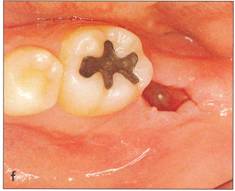

Fi 545e45f g 5-2i The recipient site right before transplant procedure (2 weeks after extraction of the first molar). |

f |

Fi 545e45f g 5-2j After suturing of the gingival flap and fixation of the donor tooth using sutures. |